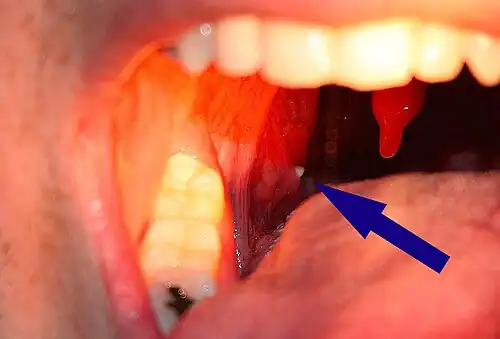

![]() | |

| A tonsillolith lodged in the tonsillar crypt | |